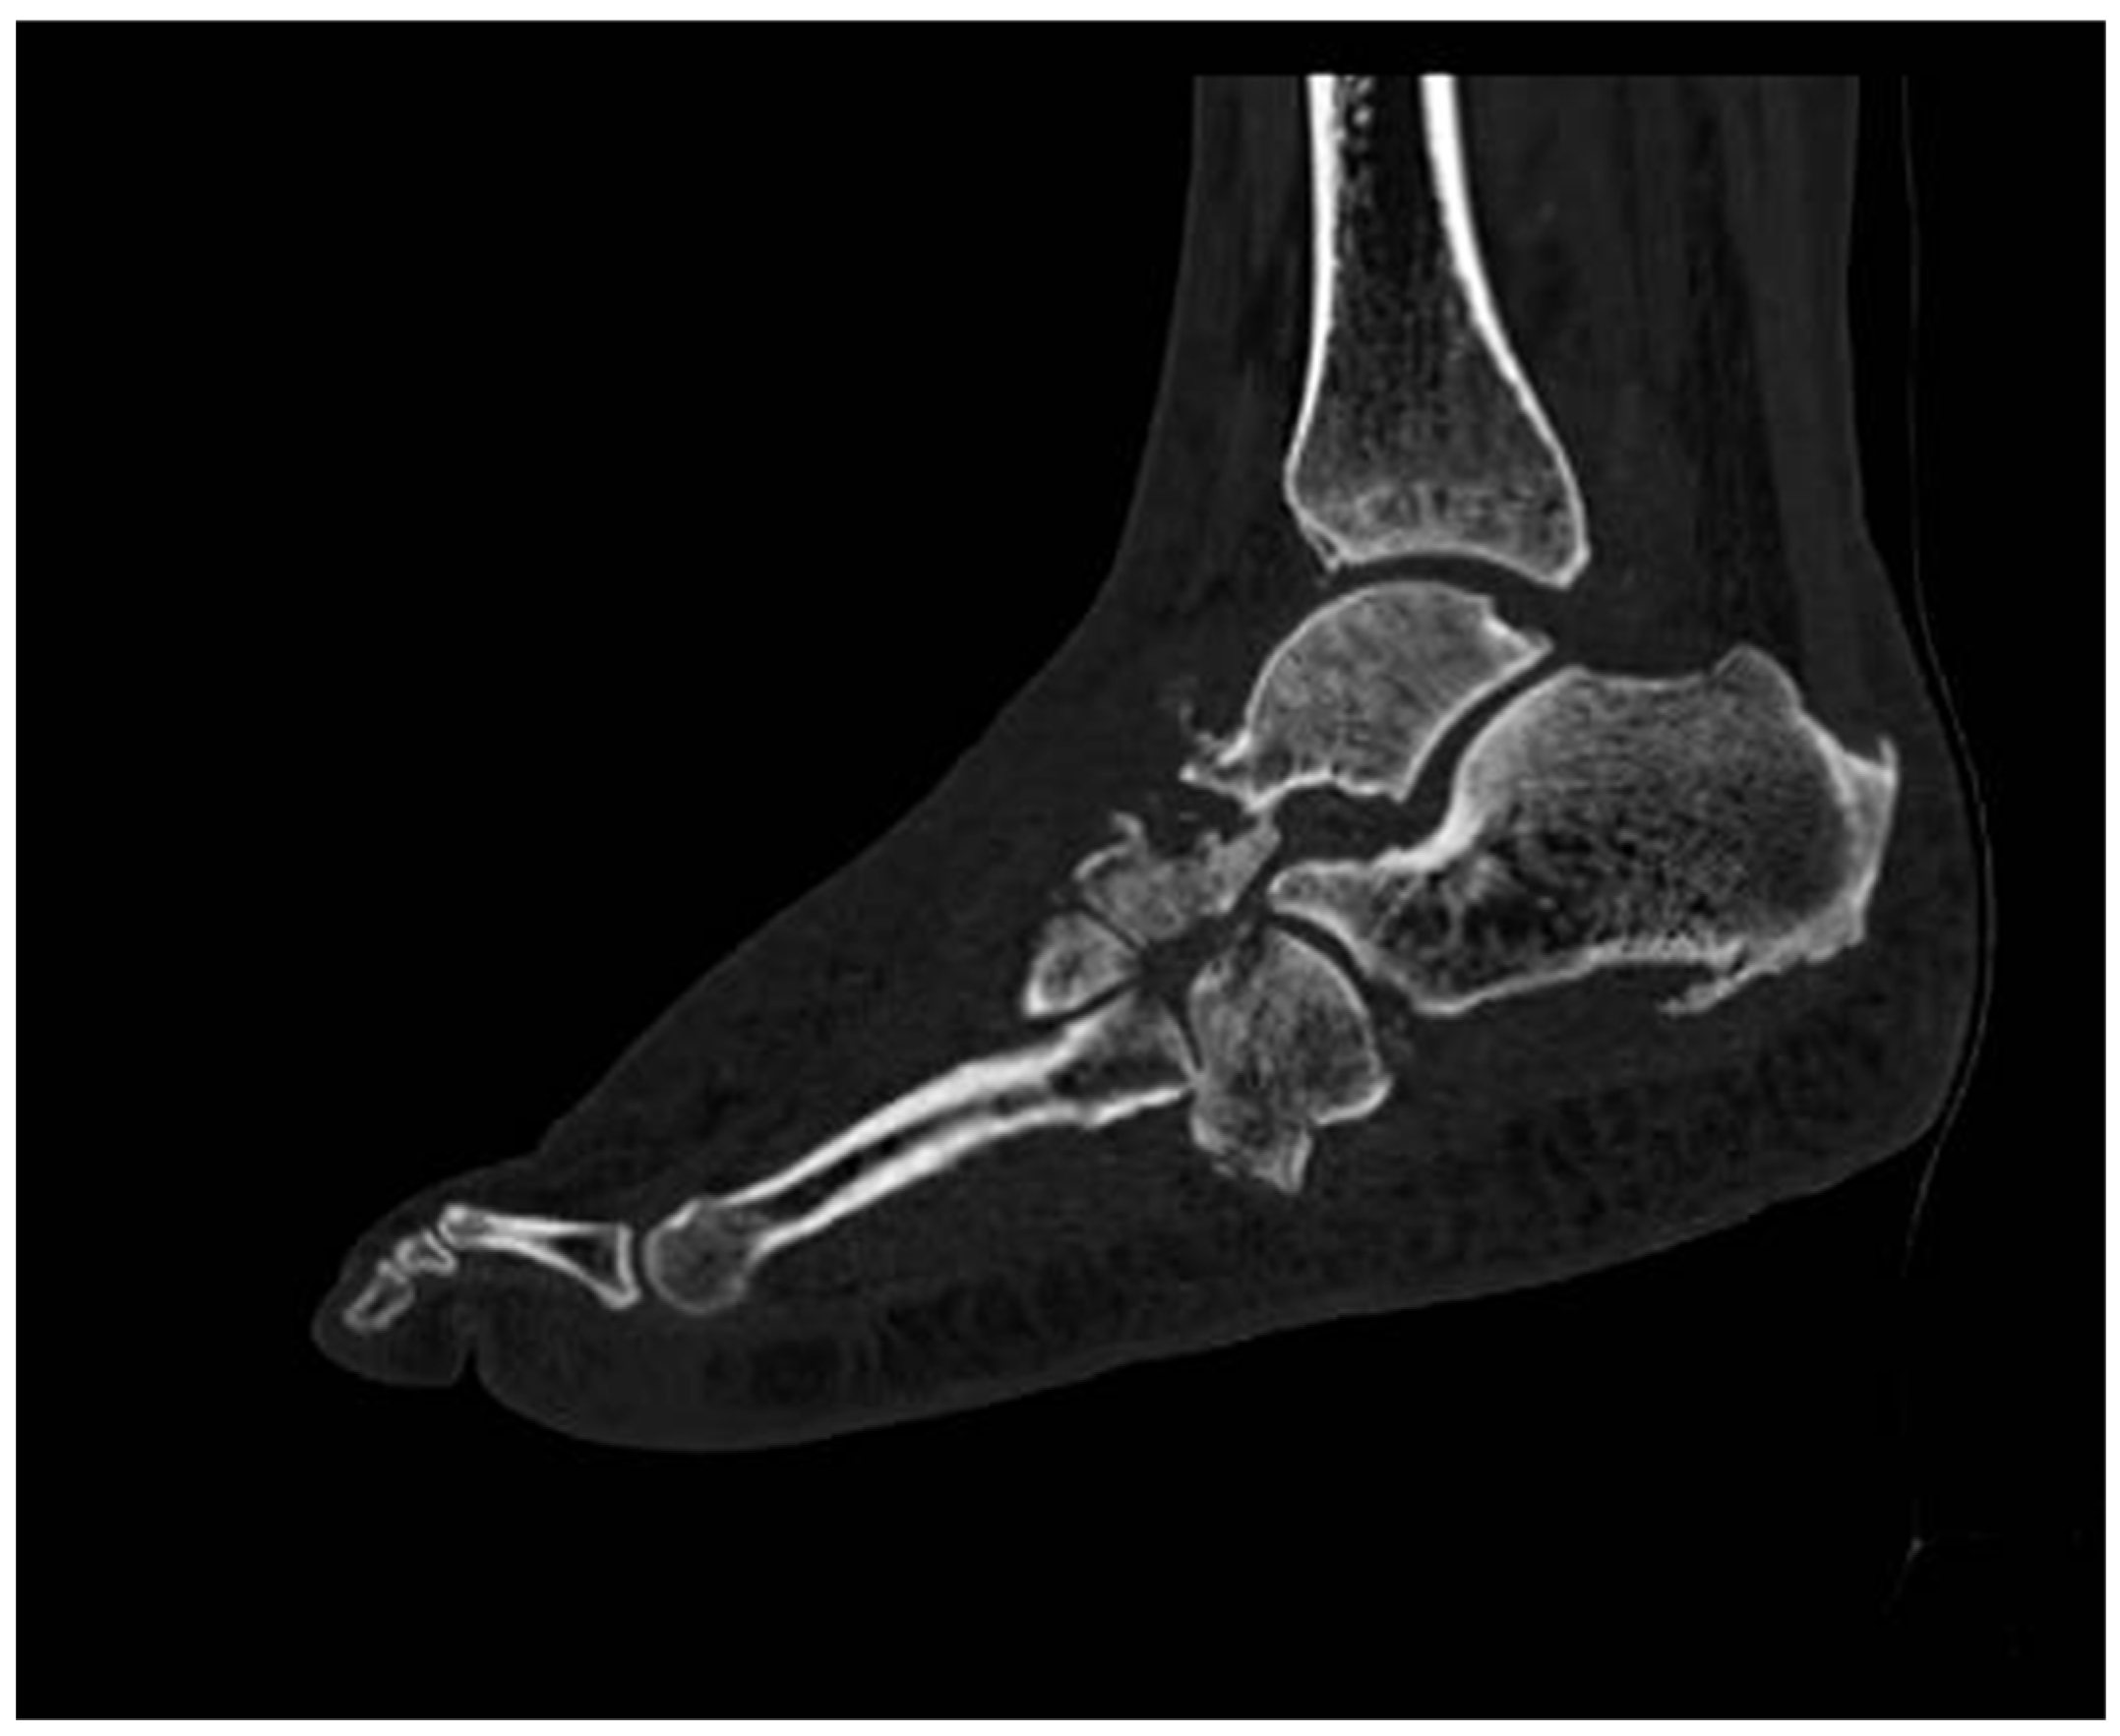

5. Computed Tomography Scan